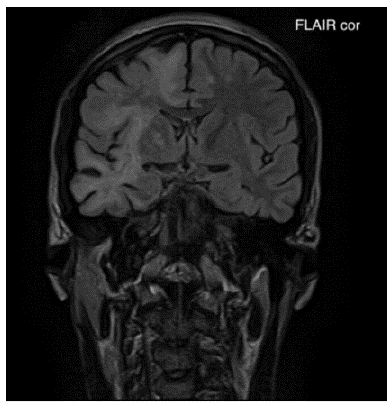

Ante el cuadro clínico y los hallazgos descritos en el examen físico se realizó una imagen de resonancia magnética (IRM) cerebral contrastada (figuras 1-3) en la cual se documentó la presencia de hiperintensidades extensas a nivel subcortical que comprometían la sustancia blanca hemisférica cerebral derecha con una distribución en los lóbulos frontal, parietal y temporal. Adicionalmente, se observó compromiso de la sustancia blanca en la región frontotemporal izquierda que comprometía las fibras en U. No se identificaron áreas de sangrado ni tampoco la presencia de masas ni realces anormales con el medio de contraste.

Figura 1A Imagen de resonancia magnética cerebral contrastada corte coronal en secuencia FLAIR: Lesiones hiperintensas de extenso compromiso de la sustancia blanca subcortical difusa bilateral de predominio derecho en lóbulo frontal, parietal y temporal.

Por medio de la IRM cerebral contrastada, especialmente en la secuenciación potenciada en T2 y recuperación de la inversión atenuada de fluido (FLAIR por sus siglas en inglés), fue posible identificar las lesiones típicas de la enfermedad. Se trata de lesiones múltiples bilaterales, hiperintensas, asimétricas, de morfología irregular, que comprometen la sustancia blanca subcortical y yuxtacortical del cerebro, incluyendo las fibras en U, delineando los bordes de la corteza sin producir efecto de masa ni realce con el medio de contraste 3,8,9. En la secuenciación potenciada en T1 estas lesiones se presentan hipointensas.